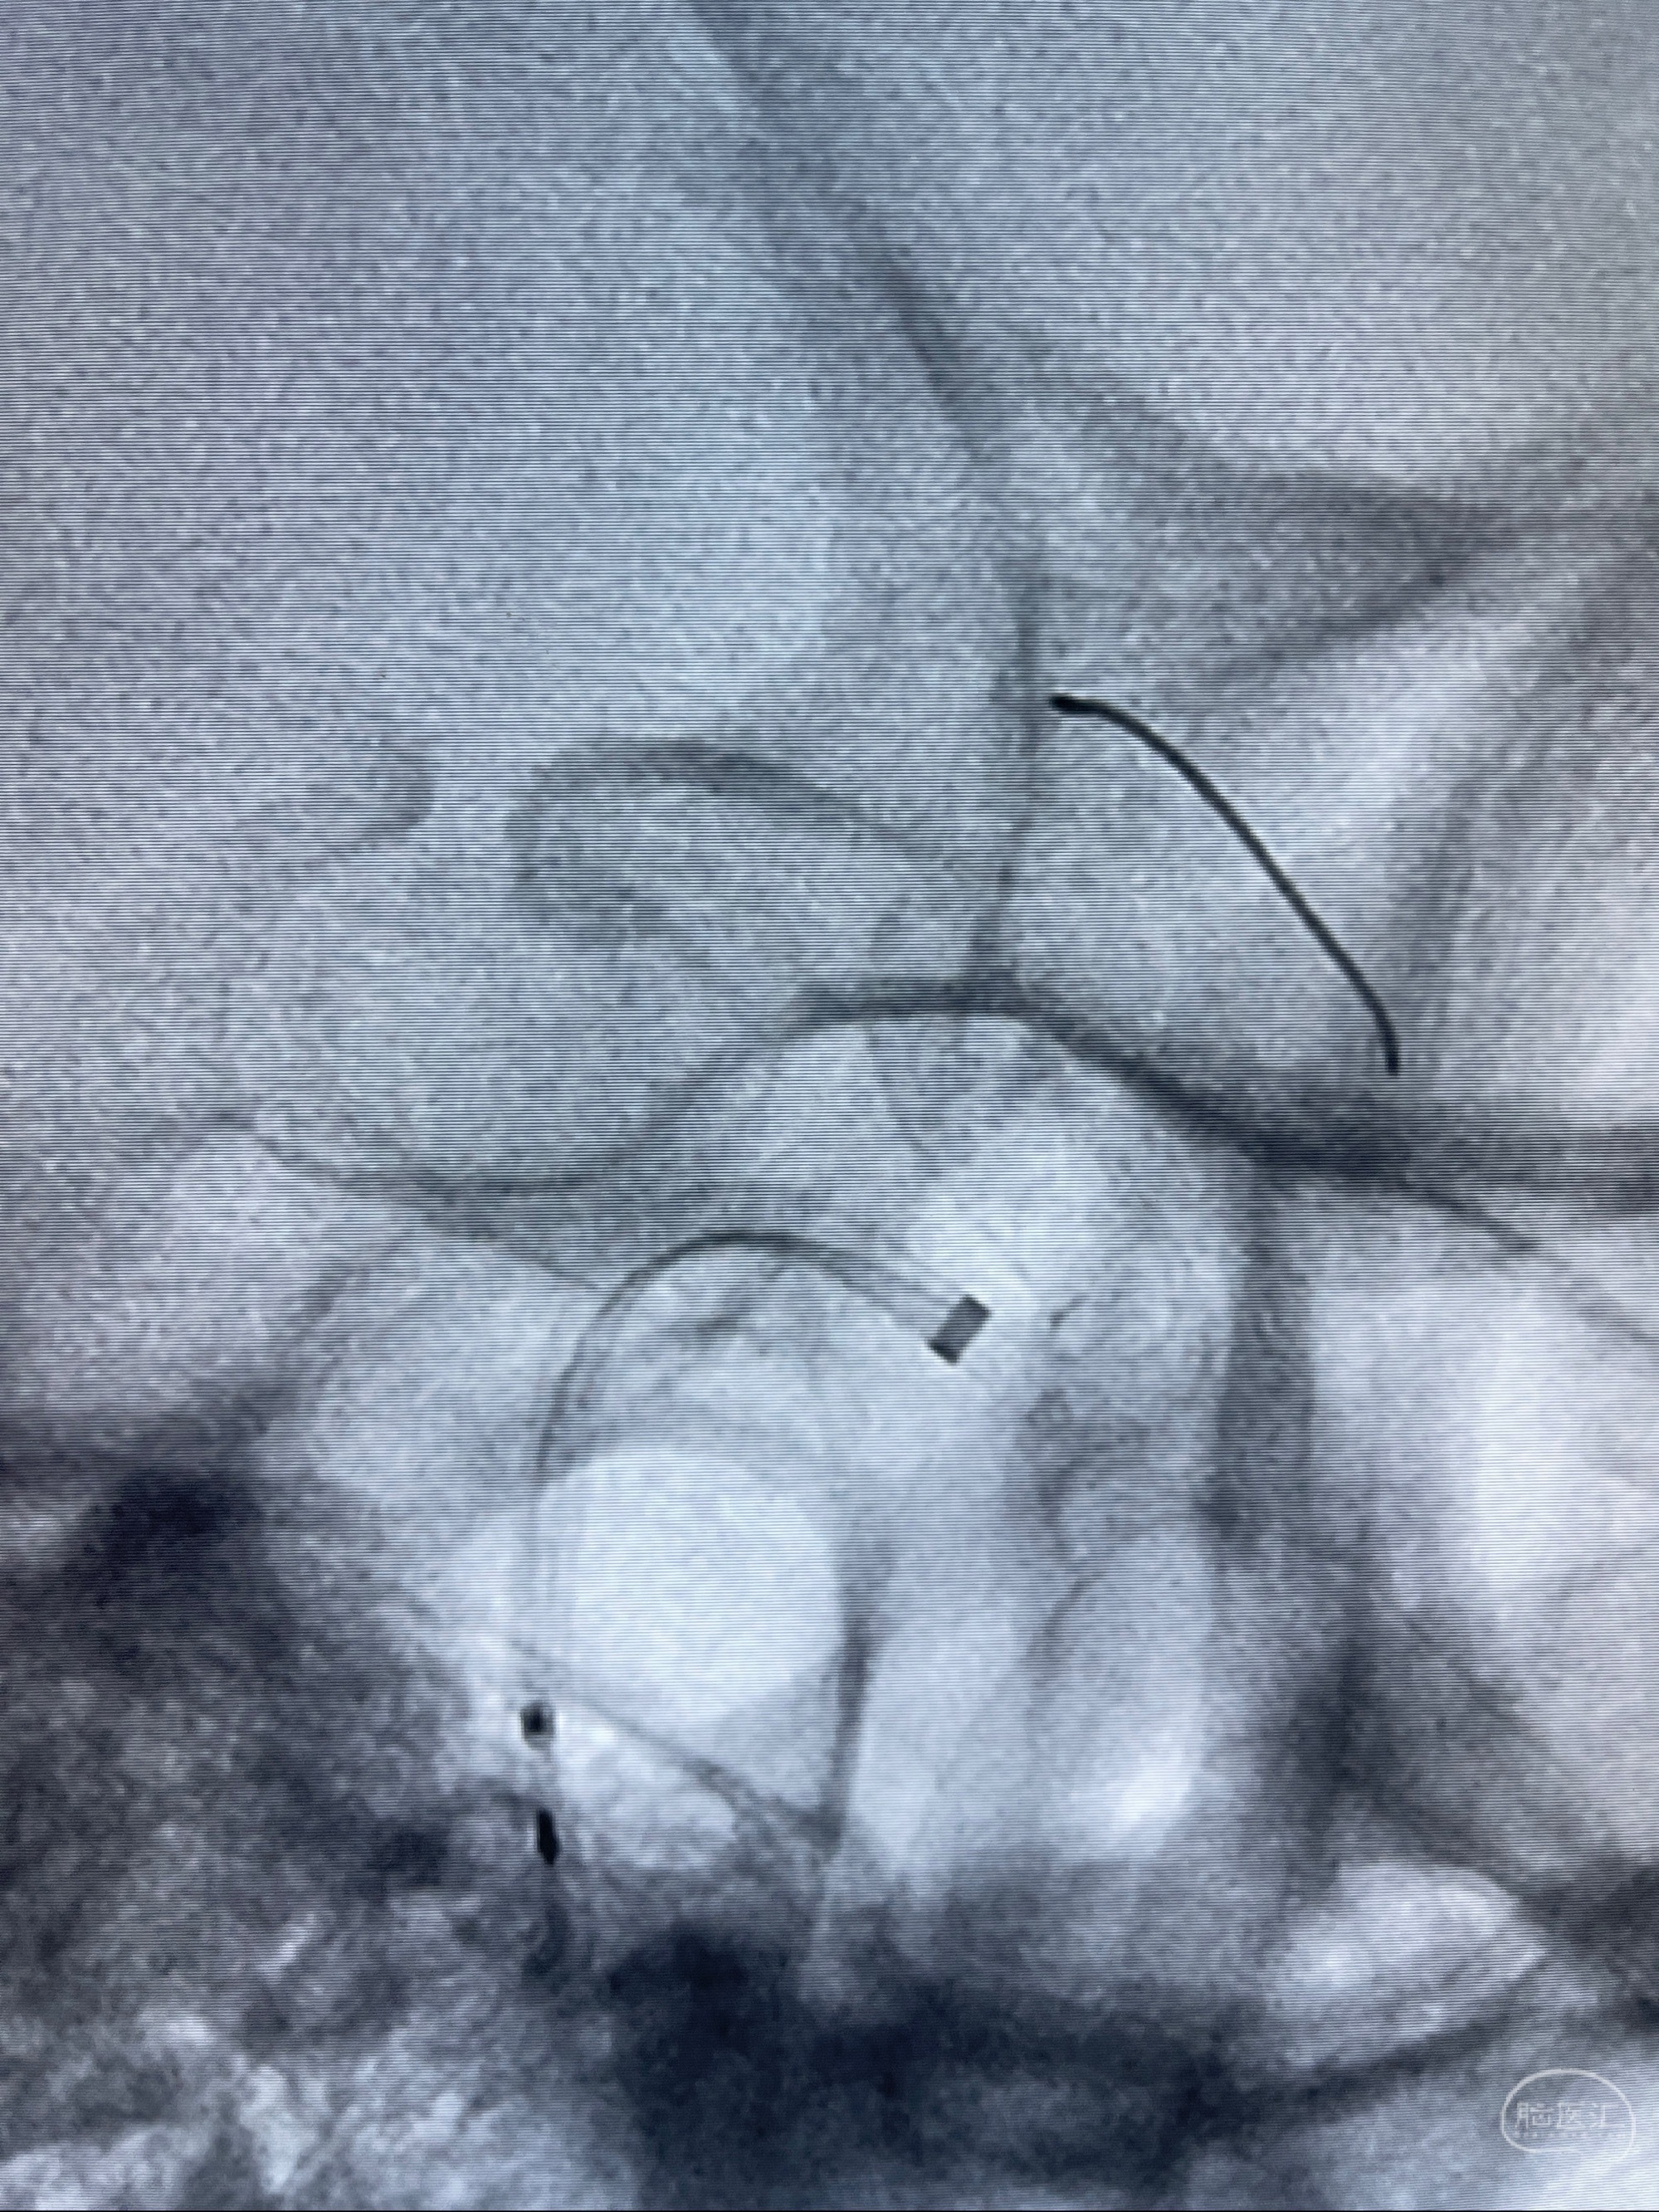

2023-07-27全脑血管造影:双侧颈内动脉眼动脉段动脉瘤,右侧较大

2023-08-01全麻下行双侧颈眼动脉瘤支架辅助栓塞

- pipeling4.5-20mm

- pipeline 4.0-20mm